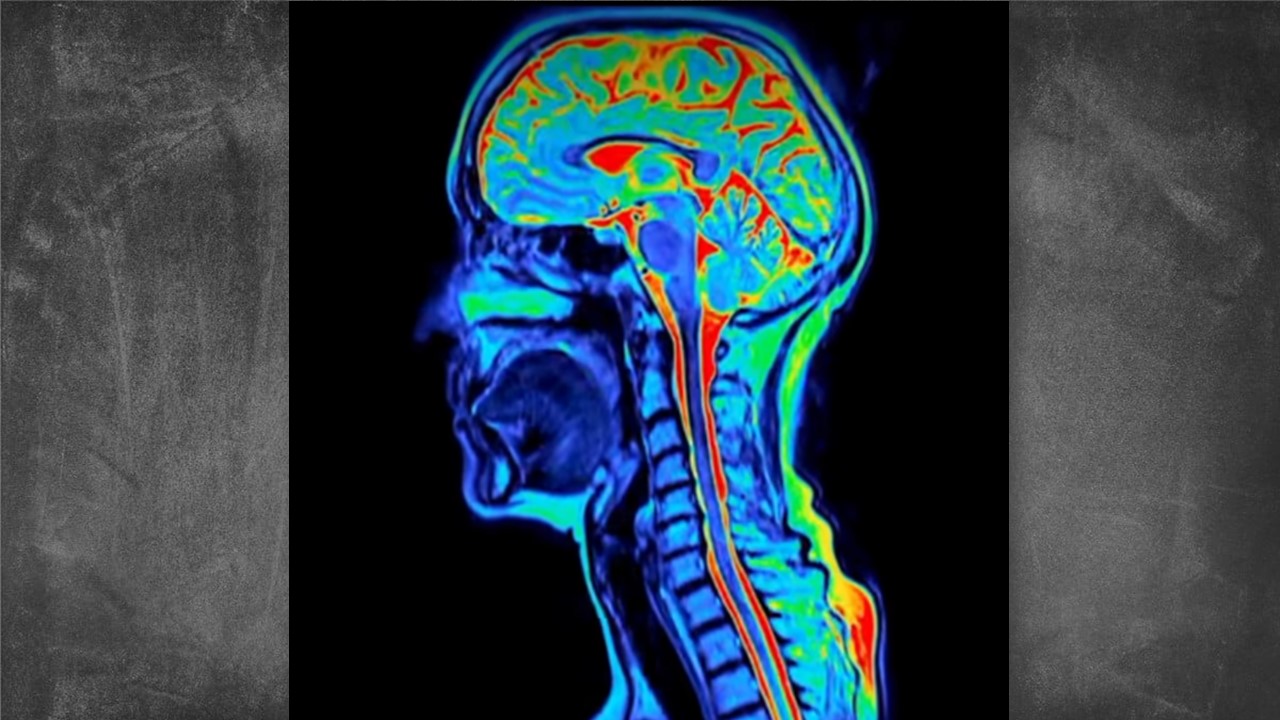

Um estudo conduzido por pesquisadores da Universidade de Cambridge, no Reino Unido, trouxe novas perspectivas sobre o desenvolvimento humano ao revelar que o cérebro passa por cinco fases distintas ao longo da vida, marcadas por transformações significativas aos 9, 32, 66 e 83 anos. A descoberta desafia a ideia tradicional de que a maturidade cerebral ocorre no fim da adolescência.

A pesquisa analisou exames cerebrais de cerca de 4 mil pessoas, com idades entre a infância e os 90 anos. O mapeamento das conexões neurais mostrou que o cérebro continua em uma espécie de “fase adolescente” até o início dos 30 anos  período em que atinge seu desempenho máximo, segundo os cientistas.

As imagens revelaram que, até os 32 anos, há um fortalecimento constante das redes neurais responsáveis por raciocínio, tomada de decisão, regulação emocional e flexibilidade cognitiva. Só então o cérebro alcançaria seu “pico” de funcionamento, antes de iniciar ciclos naturais de reorganização nas décadas seguintes.